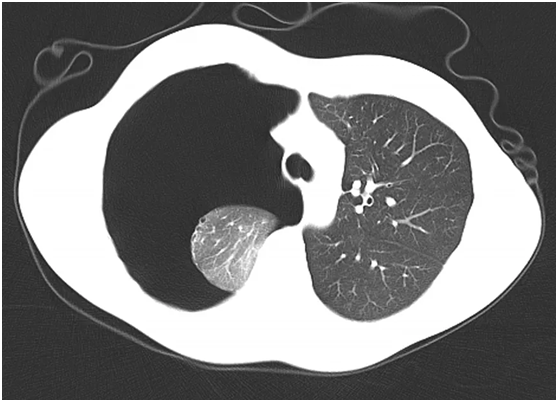

九月的阳光,温暖而明媚,洒落在校园的每一个角落。在这个充满希望的季节里,各个学校迎来了新学期的开始。近日,就读某大学的18岁大一新生小李在辅导员和室友的陪伴下,来到大连市第五人民医院胸外一科就诊。小李一脸痛苦、呼吸急促、面色苍白、嘴唇发紫,经过医生快速了解病史并行CT检查后发现,小李的右侧肺患了气胸,肺已经被压缩了90%!医生进一步询问病史后得知,这是小李第二次犯气胸了,第一次犯病的时候,肺组织被压缩了约20%,当时采取了保守观察治疗。

纵膈和气管移位